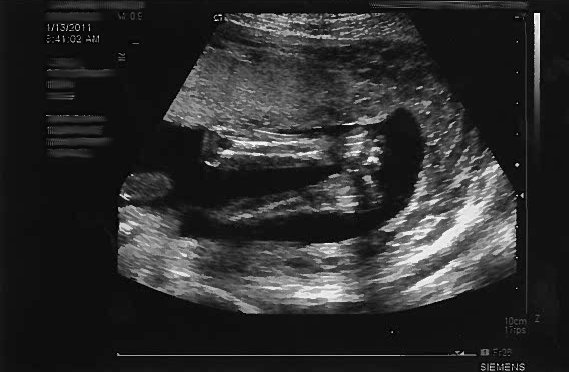

13 January 2011 – Another FANTASTIC day! You had your “big” photo shoot!

Mom & Dad went to this super cutting-edge, hi-tech medical appointment. The person in the medical office used a magic wand on Mom’s belly to create images of you inside.

It was your 20-week “ultrasound” (or “Fetal Survey” as they say in the obstetrical world). Basically they used cyclic sound pressure with a frequency greater than the upper limit of human hearing. Although this limit varies from person to person, it is approximately 20 kilohertz (20,000 hertz), but you know this already, of course.

Mom had SUCH a fun time seeing the detail that goes into the ultrasound and your dad asked so many questions. Being that your mom works closely with the perinatology office that did the ultrasound, your parents felt they got a little VIP treatment during the appointment. One of your mom’s favorite perinatologists, Dr. Harding, read the ultrasound and was happy to tell us you look PERFECT! The ultrasonographer, Allison, said you should be in a textbook, which made your dad VERY proud. Your mom jokingly reminded your dad that being in medical textbooks isn’t always a good thing… but we know you’re happy and healthy in there!